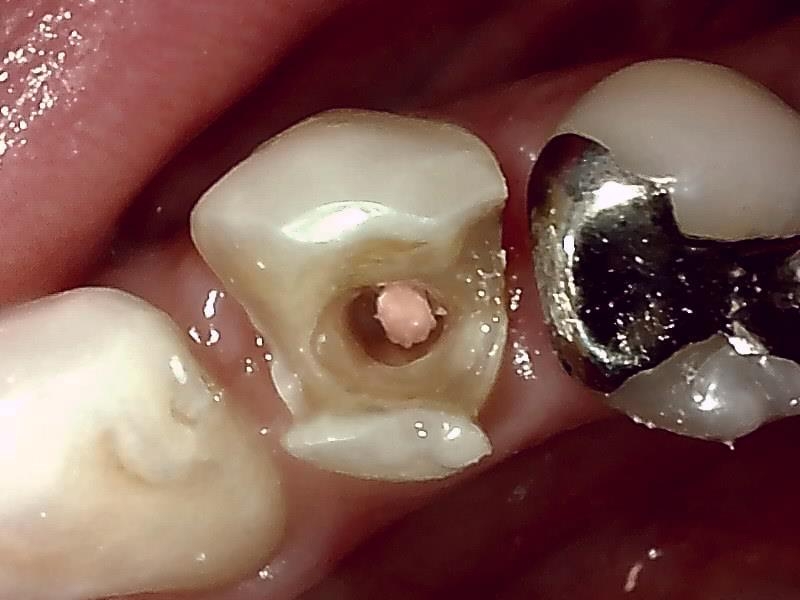

不適合な金属の詰め物の除去。

根管充填後の写真